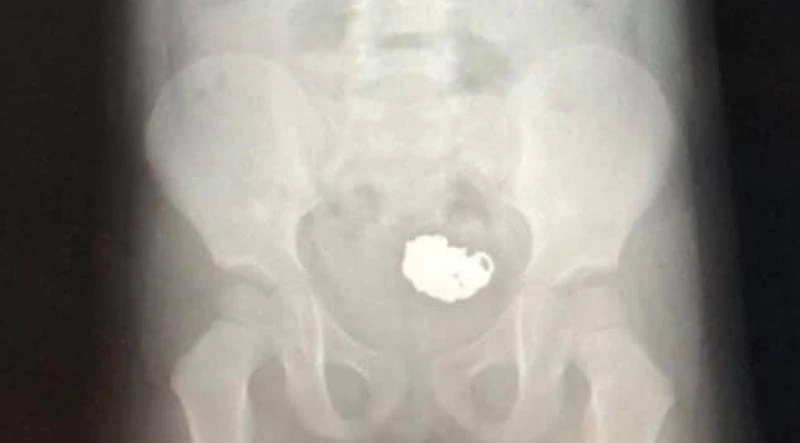

Từ việc "bị mất" vòng bạc, bé gái 3 tuổi được đưa đến bệnh viện chụp X-quang cho thấy ở phần ruột già của bé có dị vật. Ảnh: CT.

BS Nguyễn Cảnh Tùng - BV Đa khoa 115 Nghệ An cho biết: Kết quả kiểm tra cho thấy phần ruột già của bé có dị vật nghi là chiếc vòng bạc và phải chờ di vật đó đào thải ra khỏi cơ thể. Sau 3 ngày người thân và các y, BS lo lắng chờ đợi thì bé đã đi ngoài ra chiếc vòng bạc lẫn với phân. Chiếc vòng bạc vẫn còn nguyên, không bị bào mòn.